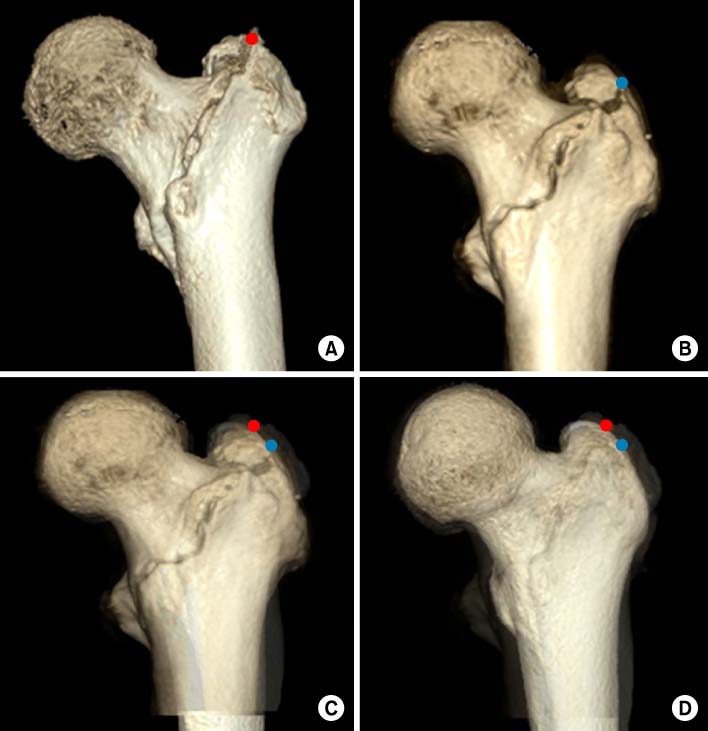

*Vertical distance from greater trochanter to fracture line. †Vertical distance from proximal boundary of lesser trochanter to fracture line. ‡The angle between the fracture line of the distal fragment and anatomical axis of the femur.